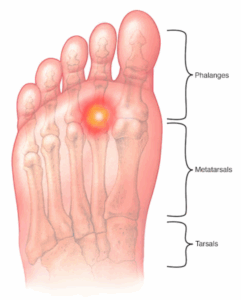

Metatarsalgia

Metatarsalgia (met-uh-tahr-SAL-juh) is a condition in which the ball of the foot becomes painful and irritated. Metatarsalgia results from activities that involve running and jumping.

Morton’s neuroma

Morton neuroma is a damaged, enlarged nerve that causes pain on the bottom of the forefoot, usually in the area behind the third and fourth toes. The pain is usually sharp or burning. There may be pain, tingling or numbness spreading into these toes.